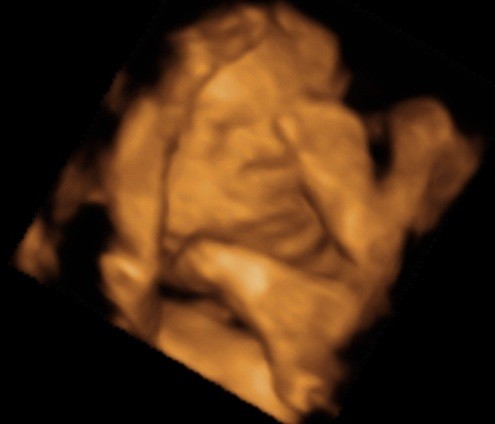

ślicznyNie wiem, ktory temat odpowiedni, wiec wstawie fotki naszego synka tutaj (nie sa to medyczne skany, wiec watek lekarski chyba nie pasuje, nie sa to tez zdjecia brzuszka...)

Zobacz załącznik 435455

Zobacz załącznik 435456

Zobacz załącznik 435457

Zobacz załącznik 435458

Zobacz załącznik 435459